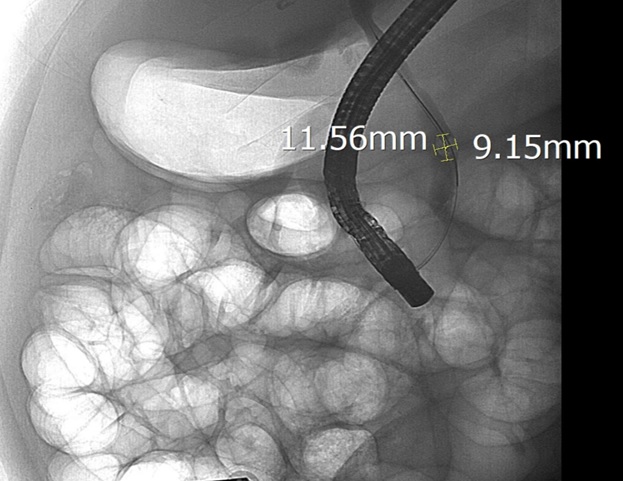

Hình ảnh sỏi ống mật chủ được lộ rõ dưới chụp DSA. Ảnh: BVCC

Sau khi hội chẩn, các bác sĩ Khoa Nội Tiêu hóa đã chỉ định nội soi mật tụy ngược dòng (ERCP) dưới hướng dẫn của hệ thống chụp mạch số hóa xóa nền (DSA). Trong quá trình can thiệp, ê-kíp đã lấy thành công viên sỏi kích thước 11,5 x 9 mm, giải phóng tình trạng tắc mật.